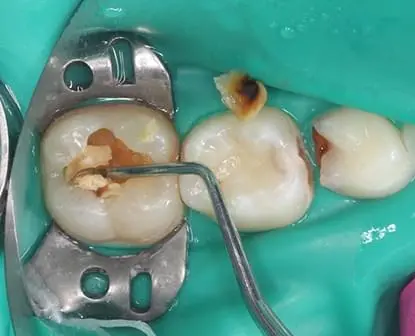

Якісна ізоляція робочого поля - один із пропускних пунктів до якісної, прогнозованої, безпечної та якісної дитячої стоматології. Коли дитячий стоматолог впроваджує кофердам до своєї рутинної практики, його робота починає набувати нової якості. Ефективна ізоляція - це можливість надати стоматологічну допомогу вищого рівня нашим маленьким пацієнтам і при цьому отримати більше задоволення від роботи. Тому цю тему варто освоїти кожному дитячому стоматологу, аби перевести стоматологічний прийом дітей прийом на новий рівень.

Карієс - найпоширеніша хвороба на планеті. Починається він, на жаль, найчастіше в дитинстві. Однак саме в дитинстві можна максимально ефективно йому запобігти і таким чином провести лікувально-профілактичні заходи, щоб у майбутньому зберегти стоматологічне здоров'я. В нашому курсі ми зробили акценти саме на лікуванні карієсу саме у дітей. На відеодемонстраціях ми детально демонструємо етапи і послідовність відновлення уражених твердих тканин різних груп зубів у дітей, що допоможе максимально освоїти тематику карієсології та робить курс максимально практичним.